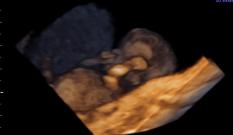

Ainda é possível fazer o ultrassom do primeiro trimestre e, neste caso, tudo o que explicamos na semana anterior segue valendo. Na maioria das pacientes, os primeiros exames da gravidez já foram feitos — já passamos por um dos principais momentos em que se verificou que está tudo bem.

| Já passamos por um dos grandes momentos da gravidez, o ultrassom do primeiro trimestre, no qual se verificou que estava tudo bem. |